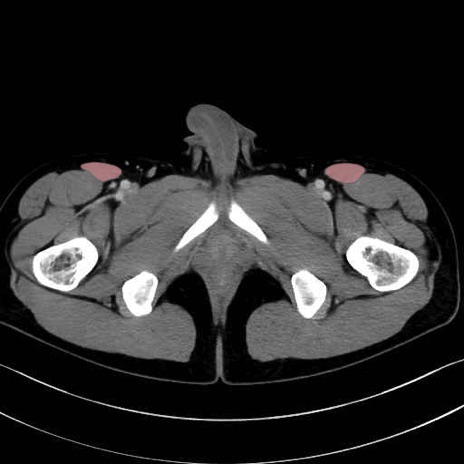

内閉鎖筋 (Obturator internus)

外閉鎖筋 (Obturator externus)

縫工筋 (Sartorius)